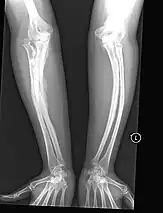

X-rays of three people with OI type V: a newborn, a child, and an adult. Evident are somewhat deformed long bones with widened metaphyses.

• Type V Having the same clinical features as type IV, it can be clinically distinguished by observing a "mesh-like" appearance to a bone biopsy under a microscope. Type V can be further distinguished from other types of OI by the "V triad": an opaque band (visible on X-ray) adjacent to the growth plates; hypertrophic calluses (abnormally large masses of bony repair tissue) which form at fracture sites during the healing process; and calcification of the interosseous membrane of the forearm,[50] which may make it difficult to turn the wrist.[1]:429

Other features of this condition may include pulled elbow, and, as in other types of OI, long bone bowing and hearing loss.[64]

Cases of this type are caused by mutations in the IFITM5 gene on chromosome 11p15.5.[64][49] The separation of type V from type IV OI, its clinical type, was initially suggested even before its genetic cause was known, by Glorieux et al. in 2000.[50][65] Type V is relatively common compared to other genetically defined types of OI—4% of OI patients at the genetics department of the Brazilian Hospital de Clínicas de Porto Alegre were found to have it.[66]